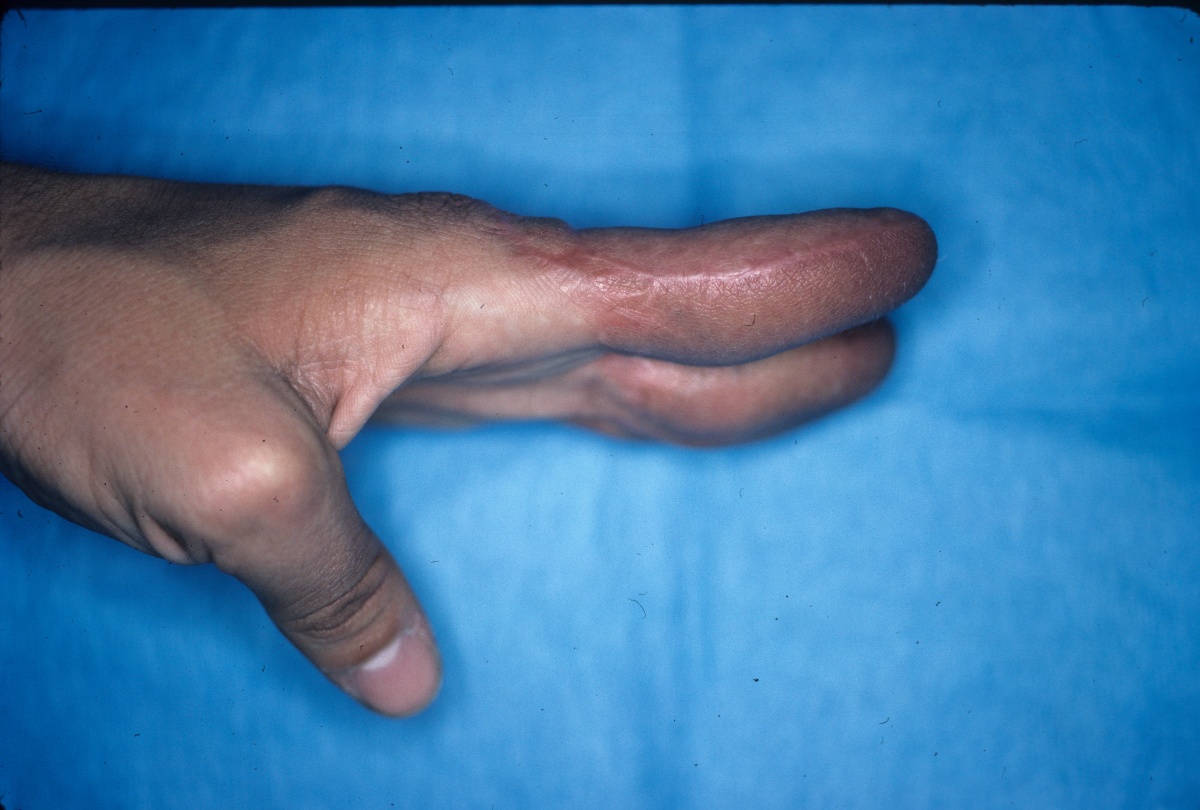

Clinical Example: Multiple finger degloving treated with medial cross arm flap and temporary syndactyly

Degloving injuries are commonly the result of industrial injuries involving high speed rollers or presses. Reconstruction is difficult because of the complexity of soft tissue loss. Skeletal elements maintain vascularity only to the most proximal phalanx distal to the most proximally degloved joint, and more distal phalanges should be discarded. This case demonstrates the first stages of reconstruction of a degloving injury of all fingers using a medial cross arm flap and temporary syndactyly within the flap.

Initial injury: